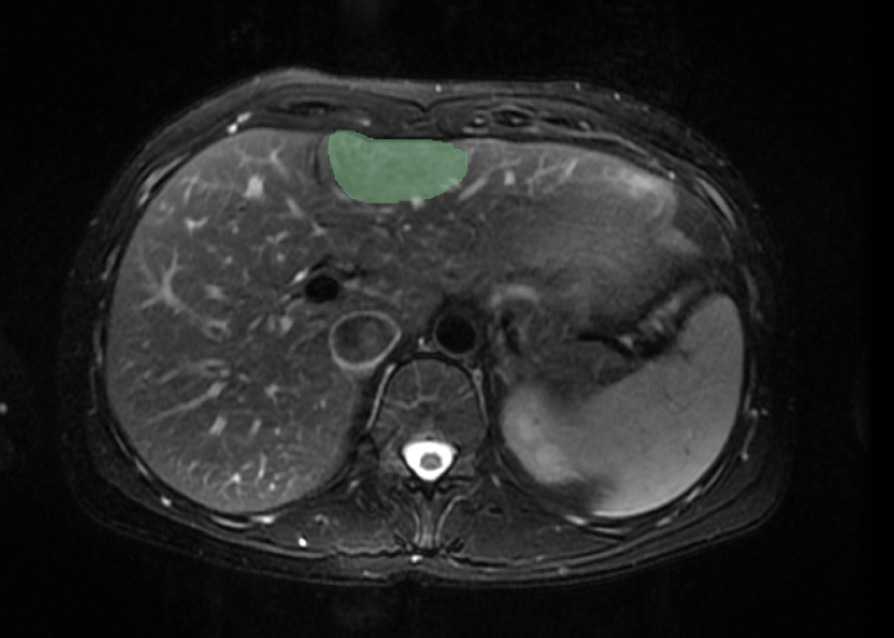

В настоящем ретроспективном кросс-секционном исследовании объектом клинико-радиомического анализа были магнитно-резонансные (МР) изображения органов брюшной полости (рис. 1), содержащие ООП, полученные из открытого набора данных WORC – WORC-Liver2 [9]. Набор данных 186 пациентов содержит сведения о поле и возрасте пациентов, данные биопсии, а также Т2-ВИ, информацию о характеристиках МР-томографов, маски ООП. Для клинико-радиомического анализа было отобрано 146 случаев. Все изображения были получены в Университете Эразма Роттердамского (Роттердам, Нидерланды) с использованием томографов 1,5 Т производства Philips (Нидерланды), Siemens (Германия) и General Electric (США) (не менее 5 случаев на тип томографа) в период с 2002 по 2018 г.

Рис. 1. Пример МР-изображения из набора данных WORC – WORC Liver (источник: https://xnat.health-ri.nl/data/projects/worc)